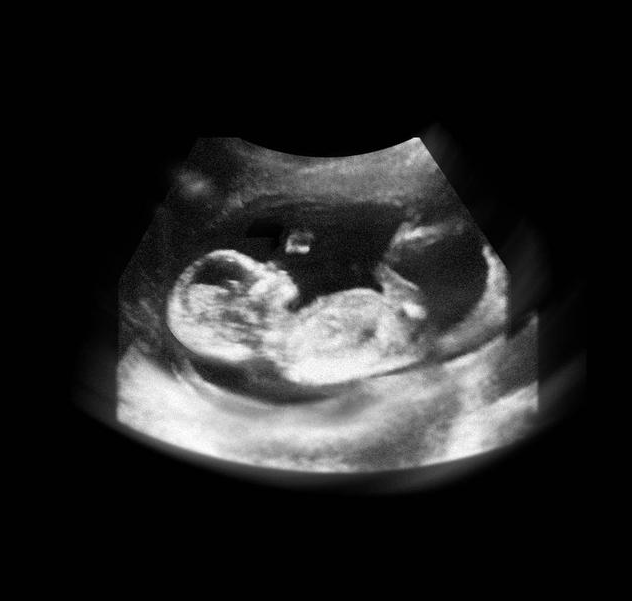

进入12周,胎儿开始在羊水中又动了,骨骼发育开始坚硬,宝宝的四肢开始做很多动作,肾脏开始分泌尿液,肝脏开始分泌胆汁,维持生命的重要器官更多地开始工作了。

13-15周,胎儿的眼睛开始转动,大脑也在飞速地发育,胎儿的小脸已经和成人差不多了,神经元开始增多,条件反射也开始增加,胎儿身材比例越来越合理了。